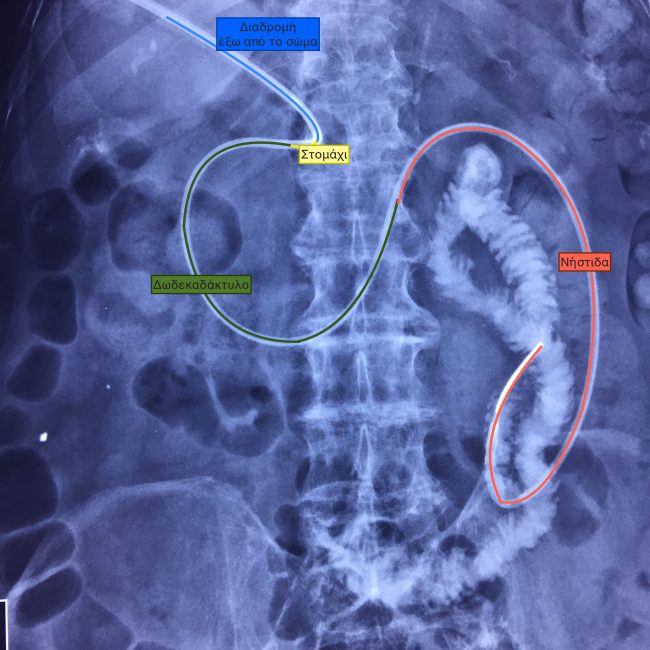

ΓΑΣΤΡΟΣΤΟΜΙΑ με επέκταση στο έντερο

Η γαστροστομια με επέκταση στο έντερο, δηλαδή η εισαγωγή καθετήρα σίτισης μέσω γαστροστομιας στο λεπτό έντερο, είναι μέθοδος που αποτρέπει τη γαστροοισοφαγική παλλινδρόμηση τροφών και όξινων γαστρικών υγρών, που θα είχε ως συνέπεια την εισρόφηση τους στους πνεύμονες.